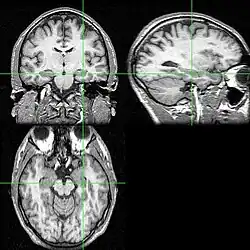

Diversos cortes de ressonância magnética com a localização do hipocampo (cruzamento das linhas verdes).